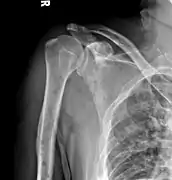

The diagnostic examination of a person with suspected multiple myeloma typically includes a skeletal survey. This is a series of X-rays of the skull, axial skeleton, and proximal long bones. Myeloma activity sometimes appears as "lytic lesions" (with local disappearance of normal bone due to resorption). And on the skull X-ray as "punched-out lesions" (raindrop skull). Lesions may also be sclerotic, which is seen as radiodense.[52] Overall, the radiodensity of myeloma is between −30 and 120 Hounsfield units (HU).[53] Magnetic resonance imaging is more sensitive than simple X-rays in the detection of lytic lesions, and may supersede a skeletal survey, especially when vertebral disease is suspected. Occasionally, a CT scan is performed to measure the size of soft-tissue plasmacytomas. Bone scans are typically not of any additional value in the workup of people with myeloma (no new bone formation; lytic lesions not well visualized on bone scan).

Multiple myeloma in the upper arm

Humerus with multiple myeloma lesions